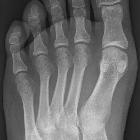

rechter Fuß. Der Fußtyp mit geradem Abschluss aller Zehen auf einer Linie wird als "Römischer Typ" bezeichnet.

Fußtyp: Die Endglieder aller Zehen schließen praktisch auf einer Linie ab, die Zehen sind gleich lang.

Fuß-Typ: Die Zehenspitzen verlaufen alle in einer geraden Linie.